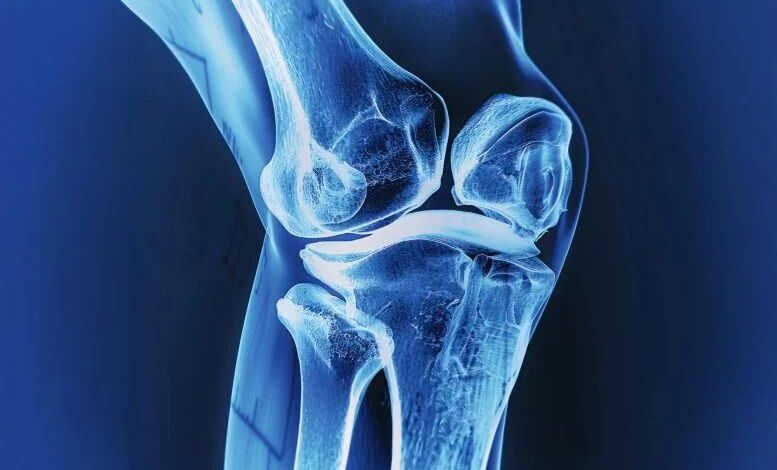

در این مطالعه، گروه پژوهشی روی عوارض رایج مرتبط با ایمپلنتهای استخوان تمرکز کرد. میلیونها نفر در سراسر جهان با ایمپلنتهای فلزی لگن یا زانو زندگی میکنند. بسیاری از این ایمپلنتها بهمرور زمان نیاز به تعمیر پیدا میکنند، زیرا یا بهخوبی با استخوان پیوند نمیخورند یا استحکام خود را از دست میدهند.